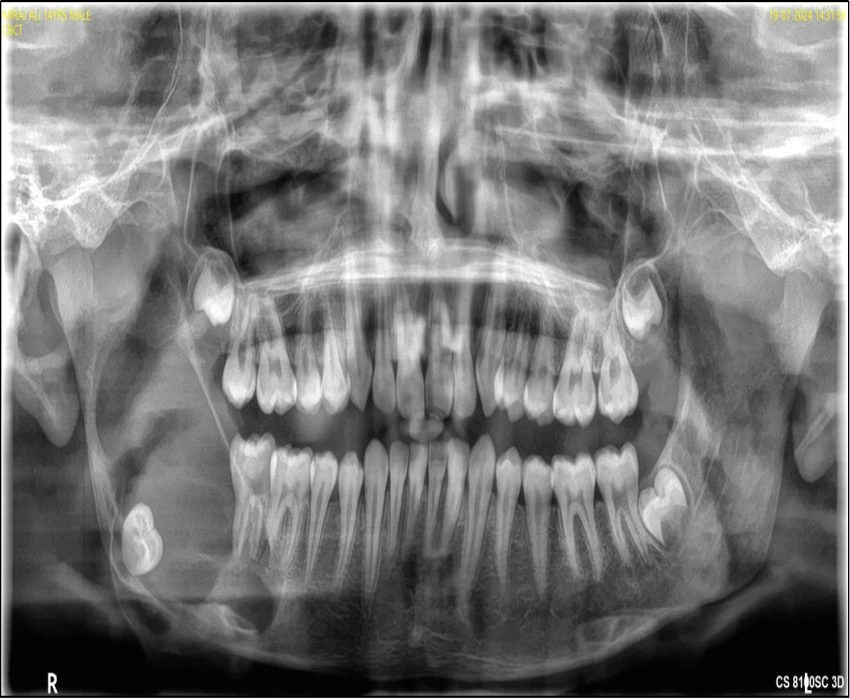

A 14 year old patient reported to the department of Oral Medicine & Radiology with a chief complaint of swelling in his right lower back region of jaw since 4 months. Provisional diagnosis was made as dentigerous cyst i.r.t. 48 based on age of the patient, location of swelling, clinical and radiographic findings. Differential diagnosis was made as Unicystic ameloblastoma (Mural) and Odontogenic keratocyst.

Histopathological report came out to be unicystic ameloblastoma with mural and intraluminal proliferation.

Unicystic ameloblastomas are seen most often in younger patients, with about 50% of all such tumors diagnosed during the second decade of life. The average age in one large series was 23 years. More than 90% of unicystic ameloblastomas are found in the mandible, usually in the posterior regions. The lesion is often asymptomatic, although large lesions may cause a painless swelling of the jaws. In mural unicystic ameloblastoma, the fibrous wall of the cyst is infiltrated by typical follicular or plexiform ameloblastoma. These tumors are usually treated as cysts by enucleation.